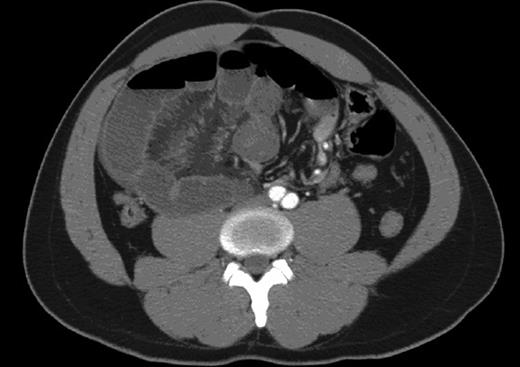

A 34-year-old man presented to the emergency department after a low velocity motor vehicle accident. He complained of severe periumbilical pain, emesis and an episode of syncope 7 hours prior at arriving to the hospital. He described his abdominal pain as constant, radiating to the right lower quadrant and associated with nausea and vomiting. His last bowel movement was prior to his presentation to the hospital. The patient described a history of intermittent, colicky periumbilical pain for the past three months. He denied any previous surgical history. He had no history of any tobacco, alcohol or recreational drug use. On physical examination, the patient was afebrile with a blood pressure of 132/76 and pulse rate of 68. Abdominal examination revealed no signs of abdominal trauma or previous surgical scars. He had a tender palpable mass in the right lower quadrant with involuntary guarding and rebound tenderness. His white blood cell count was 9 × 103/µl, and his venous lactate level was 2 mmol/l. Computed tomography of his abdomen and pelvis was done (Fig. 1). A provisional diagnosis of acute abdomen with small-bowel obstruction was made. In view of his abdominal examination and findings on the CT scan, he was taken to the operating room for an exploratory laparotomy. An encased mass of small bowel was found twisted on itself through a vent in the mesentery (Fig. 2). It initially appeared dusky but became viable after reduction and repair of the mesenteric defect. This was consistent with an internal hernia of the pericecal type.

This CT demonstrates dilated small-bowel loops and a whirling sign suggestive of mesenteric and bowel congestion with bowel thickening consistent with ischemia.